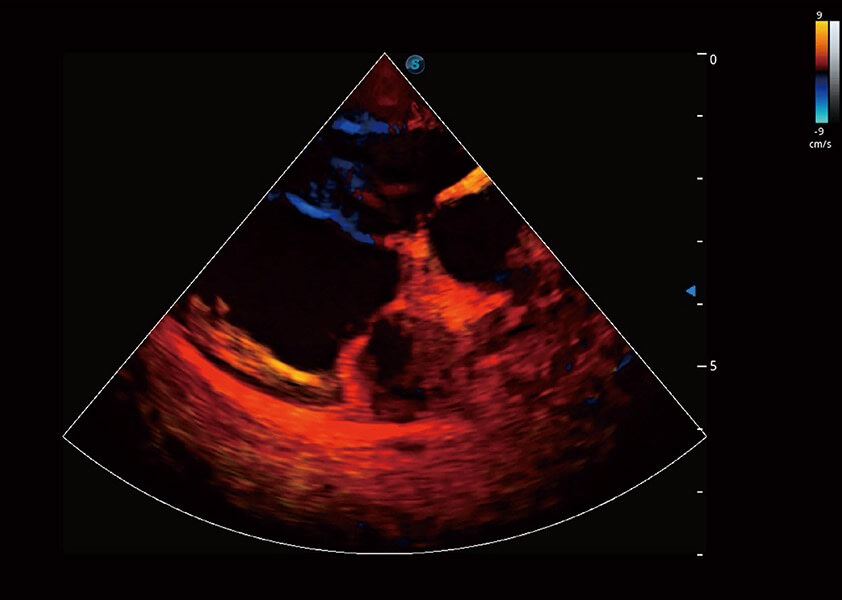

ProPet 60 作为一款高端台式动物超声设备,为动物医生的日常诊断提供了一系列贴合动物临床需求、解决临床实际问题的高级成像功能。凭借全系列高清探头,满足医生对腹部、心脏、生殖、浅表、肌骨等成像的所有需求,切实帮助您提升检查效率,提高诊断信心。

兽用彩色多普勒超声诊断系统

动物是人类最亲密的朋友和最值得信赖的伙伴。银河优越会也一直致力于探索动物专用的超声影像解决方案。 全新推出的ProPet系列,是银河优越会在动物超声影像智能化、专业化、精准化的一次跨越式革新。动物不能用言语来表述自己的不适,通过超声影像,ProPet系列搭建了动物医生与不同物种沟通的“桥梁”,为动物医生注入了“治愈之力”。